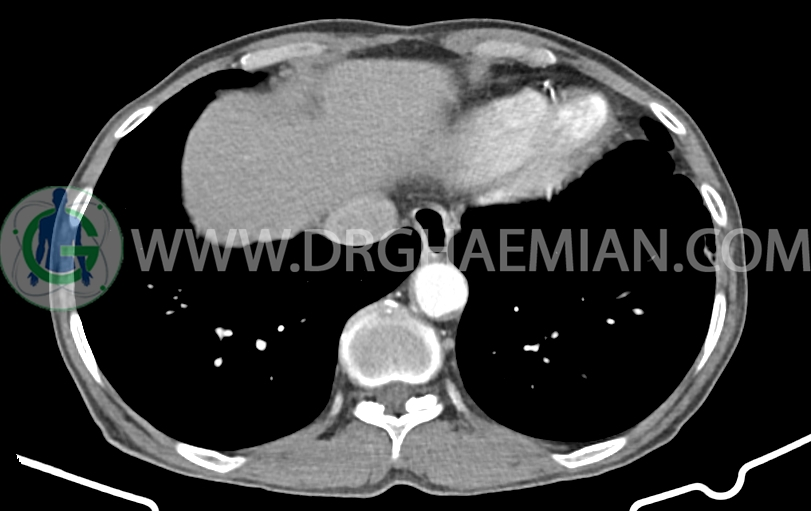

در سی تی اسکن اسپیرال ریه، مدیاستن و شکم و لگن با کنتراست خوراکی و وریدی (مولتی دیدکتور 16 با مقاطع ظریف و بازسازی های ساژیتال و کرونال) و مقایسه با سی تی اسکن 1401/06/06:

شواهدی استرنوتومی و کاردیومگالی خفیف

پنوموبینی در لوب چپ کبد مشهود است.